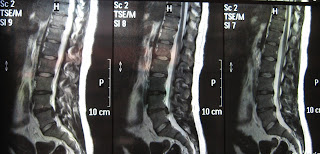

Hernia Mea De Disc Poze Rmn Pozeee Rmn Irm După 3 Ani

Aduce informatii despre tesutul din afara canalului spinal hernii de disc laterale tumori. Spuneam inca din primul paragraf ca hernia de disc este o boala din ce in ce mai intalnita in secolul 21. Hernie de disc l4 l5 mediana si paramediana dreapta transligamentara extruzata migrata inferior pana la jup atea corpului vertebral l5 ce vine in conflict cu radacina nervului l5 drept si in contact cu radacina nervului l5 stang cu amprentarea sacului dural. In 26 12 2011 nu am reusit sa ma ridic din pat am crezut ca se termina cerul dar am facut rmn in cluj si diagnosticul a fost hernie l4 l5 am luat tratament cu lirica timp de doua luni credeti ma ca am fost increzator in pastile nu cred ca la cineva i a trecut cu pastile optati pt operatie 2 zile e mai greu dar trece eu ma protejez de un an nu am lucrat nimic am luat in greutate 8 kg dar ma.